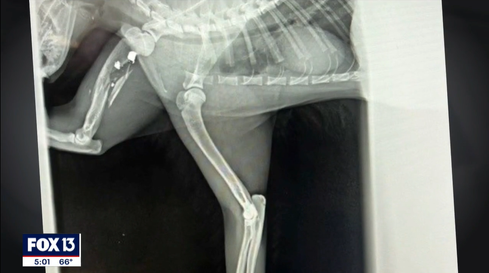

FOX 13 reports that resident Kathryn Barnes and her boyfriend look after the homeless cats in Three Lakes Mobile Home Park and said that over the last year and a half, seven cats have been shot and three have died. One of the surviving cats, Buddy, has a broken front leg and might have one of his back legs amputated after being shot either on November 5, or November 6.

The VOICELESS VICTIM was taken to RoseBird Veterinary Center in Jersey Shore where X-rays revealed the presence of two bullets lodged in the body of the dog. Only one of the two bullets could be removed. The furbaby suffered “a shattered humerus bone and has undergone surgery and continues to be hospitalized,” stated the release.